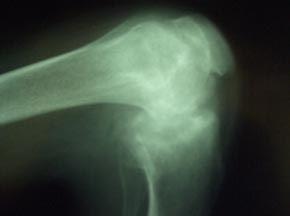

Full blood count revealed normal haemoglobin and white blood cell count. Chest X-ray was normal. Adequate knee X-rays were difficult to obtain and showed gross joint destruction with loss of joint space (Figs 2,3) and bone erosion. Radiologically and clinically the right knee was most severely affected. Testing for HIV was negative.

Figure 3: Plain lateral radiograph of the left knee.